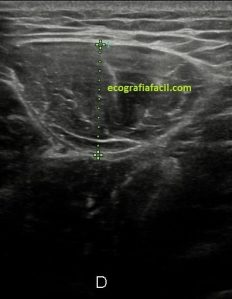

En la imagen 3 ves una imagen de un lipoma, mide 7 cms, la huella de la sonda mide 5cms, la «panoramic view» posee una regla centimetrada que sigue el contorno de la imagen, justo en la profundidad de la misma y lo marca la flecha amarilla. La profundidad la marca la flecha roja y la flecha blanca marca el rango centimetral de los 5cms, fíjate que la línea blanca es ligeramente mayor cada 5 cms. Sirve de referencia, como en la imagen 4 donde ves una colección en el glúteo de más de 10 cms.

Podemos medir valores superiores a los 15cms con alta calidad de imagen…podemos llegar a medir valores por encima de los 25 cms…es verdad que no todos los equipos tienen este ajuste ecográfico, es decir, es una aplicación y por tanto hay que pagarla.